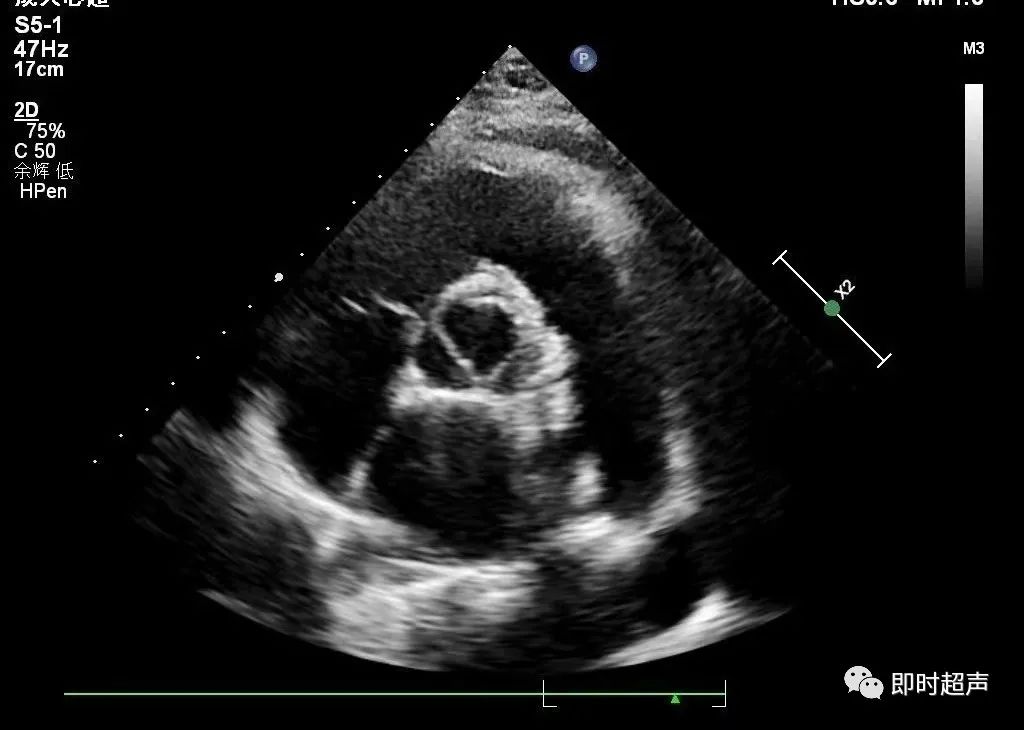

★主动脉的测量

测量切面:胸骨旁左室长轴切面;测量时相:舒张末期;测量:主动脉瓣环径、主动脉窦部内径、窦管交界处上方2cm处的近端升主动脉内径。

主动脉弓及降主动脉:胸骨上凹主动脉长轴切面舒张末期测量。